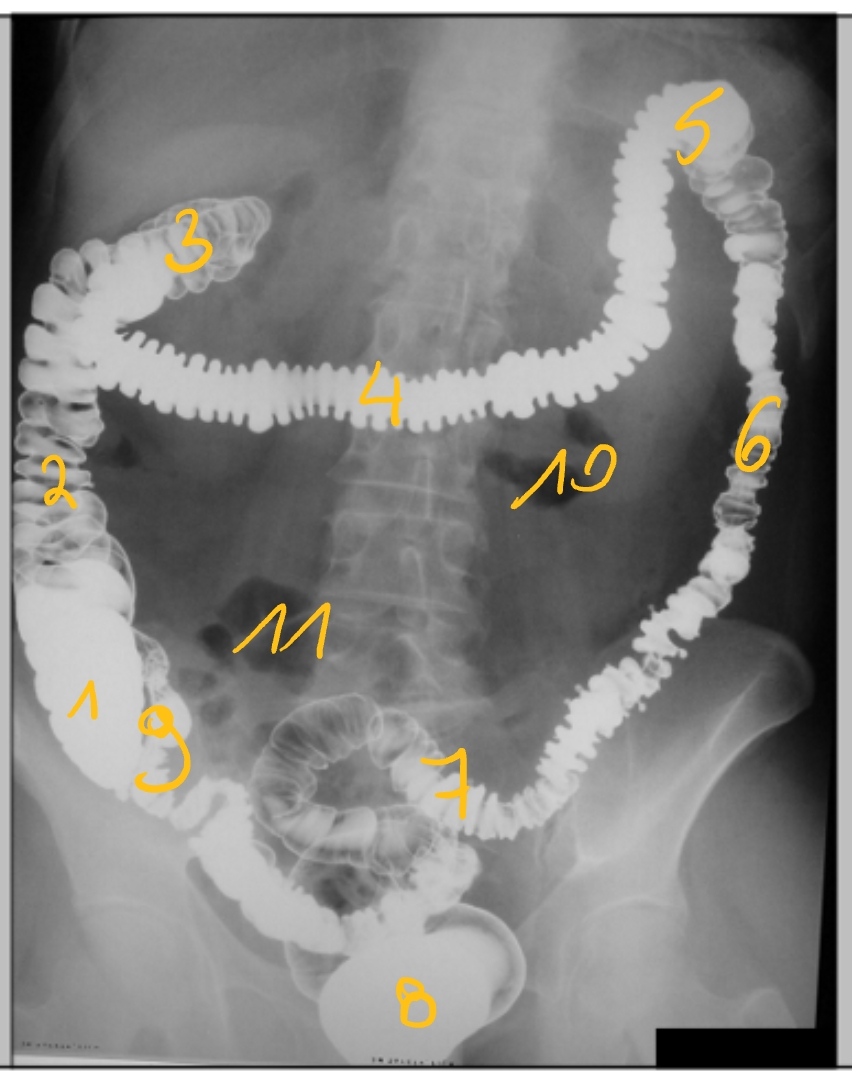

(enkelcontrast-opname)

caecum

colon ascendens

flexura coli dextra/ hepatica

colon transversum

flexura coli sinistra/ splenica

colon descendens

colon sigmoideum

rectum

laatste ileale lis

jejunum

ileum